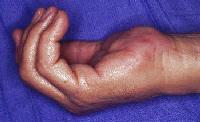

Late result.

Click for larger image